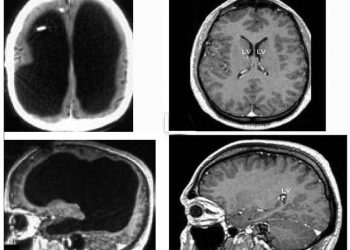

Магнитно-резонансная томограмма пациента с практически отсутствующим мозгом, но ведущим нормальную социальную жизнь. Фото: Feuillet et al./The Lancet Французский мужчина, живущий...